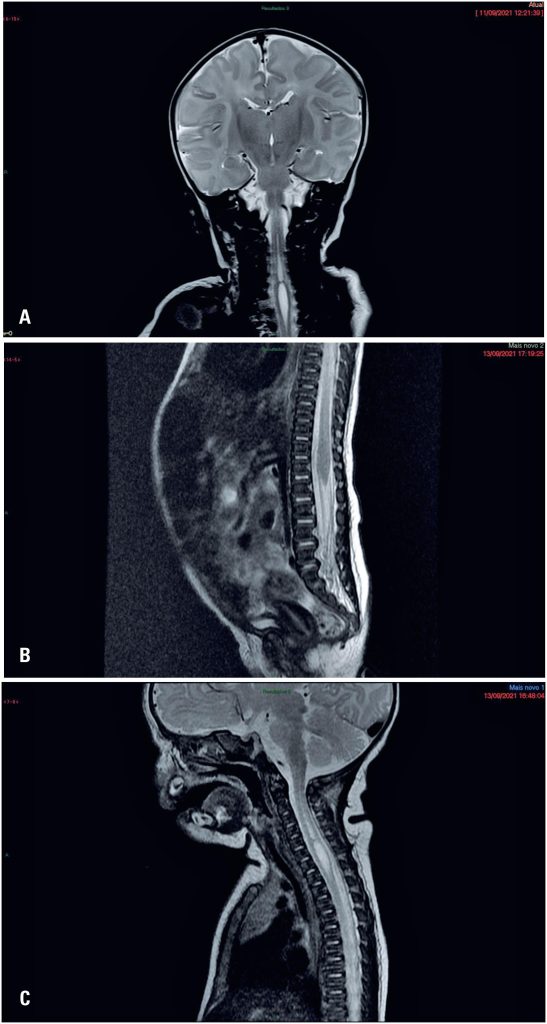

Moebius Syndrome is a genetic condition that results in inability for facial mimicry due to palsy of cranial nerves VI and VII. Syringomyelia is characterized by a dilation of the central canal in the spinal cord, and is generally asymptomatic. Both disorders are diagnosed using imaging tests. A newborn with no facial movements upon physical examination was admitted to the delivery room of our hospital. A specialist confirmed the condition to be Moebius Syndrome. Further investigation using magnetic resonance imaging indicated that syringomyelia was associated with Moebius Syndrome. Given that syringomyelia is a silent myelopathy with a possible impact on the future health of the patient, careful analysis is recommended when diagnosing Moebius Syndrome. Few similar cases have been reported to date. Further studies are warranted to determine the actual association between these two conditions. Since syringomyelia diagnoses are often made when testing for other conditions, as in this study, neurological examinations of the brain should be expanded to include the spinal cord, in order to verify the presence of coexisting disorders.